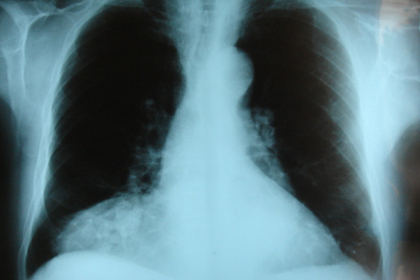

Родители Эсмы Гузель (Esma Guzel) не догадывались, что у их дочери врожденная диафрагмальная грыжа — порок развития диафрагмы, при котором грудная клетка не отделена от брюшной полости полностью. «Обычно врожденную диафрагмальную грыжу замечают во время УЗИ, — говорит мать девочки. — Во время беременности меня обследовали три раза и ничего не нашли».